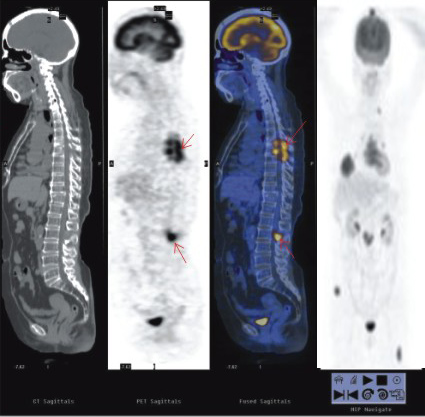

患者:男性,72歲,CT示左上肺腫塊影;PET示腫塊中向大部分壞死,周圍呈高代謝。PET-CT診斷為:左上肺癌。術(shù)后病理:鱗癌。